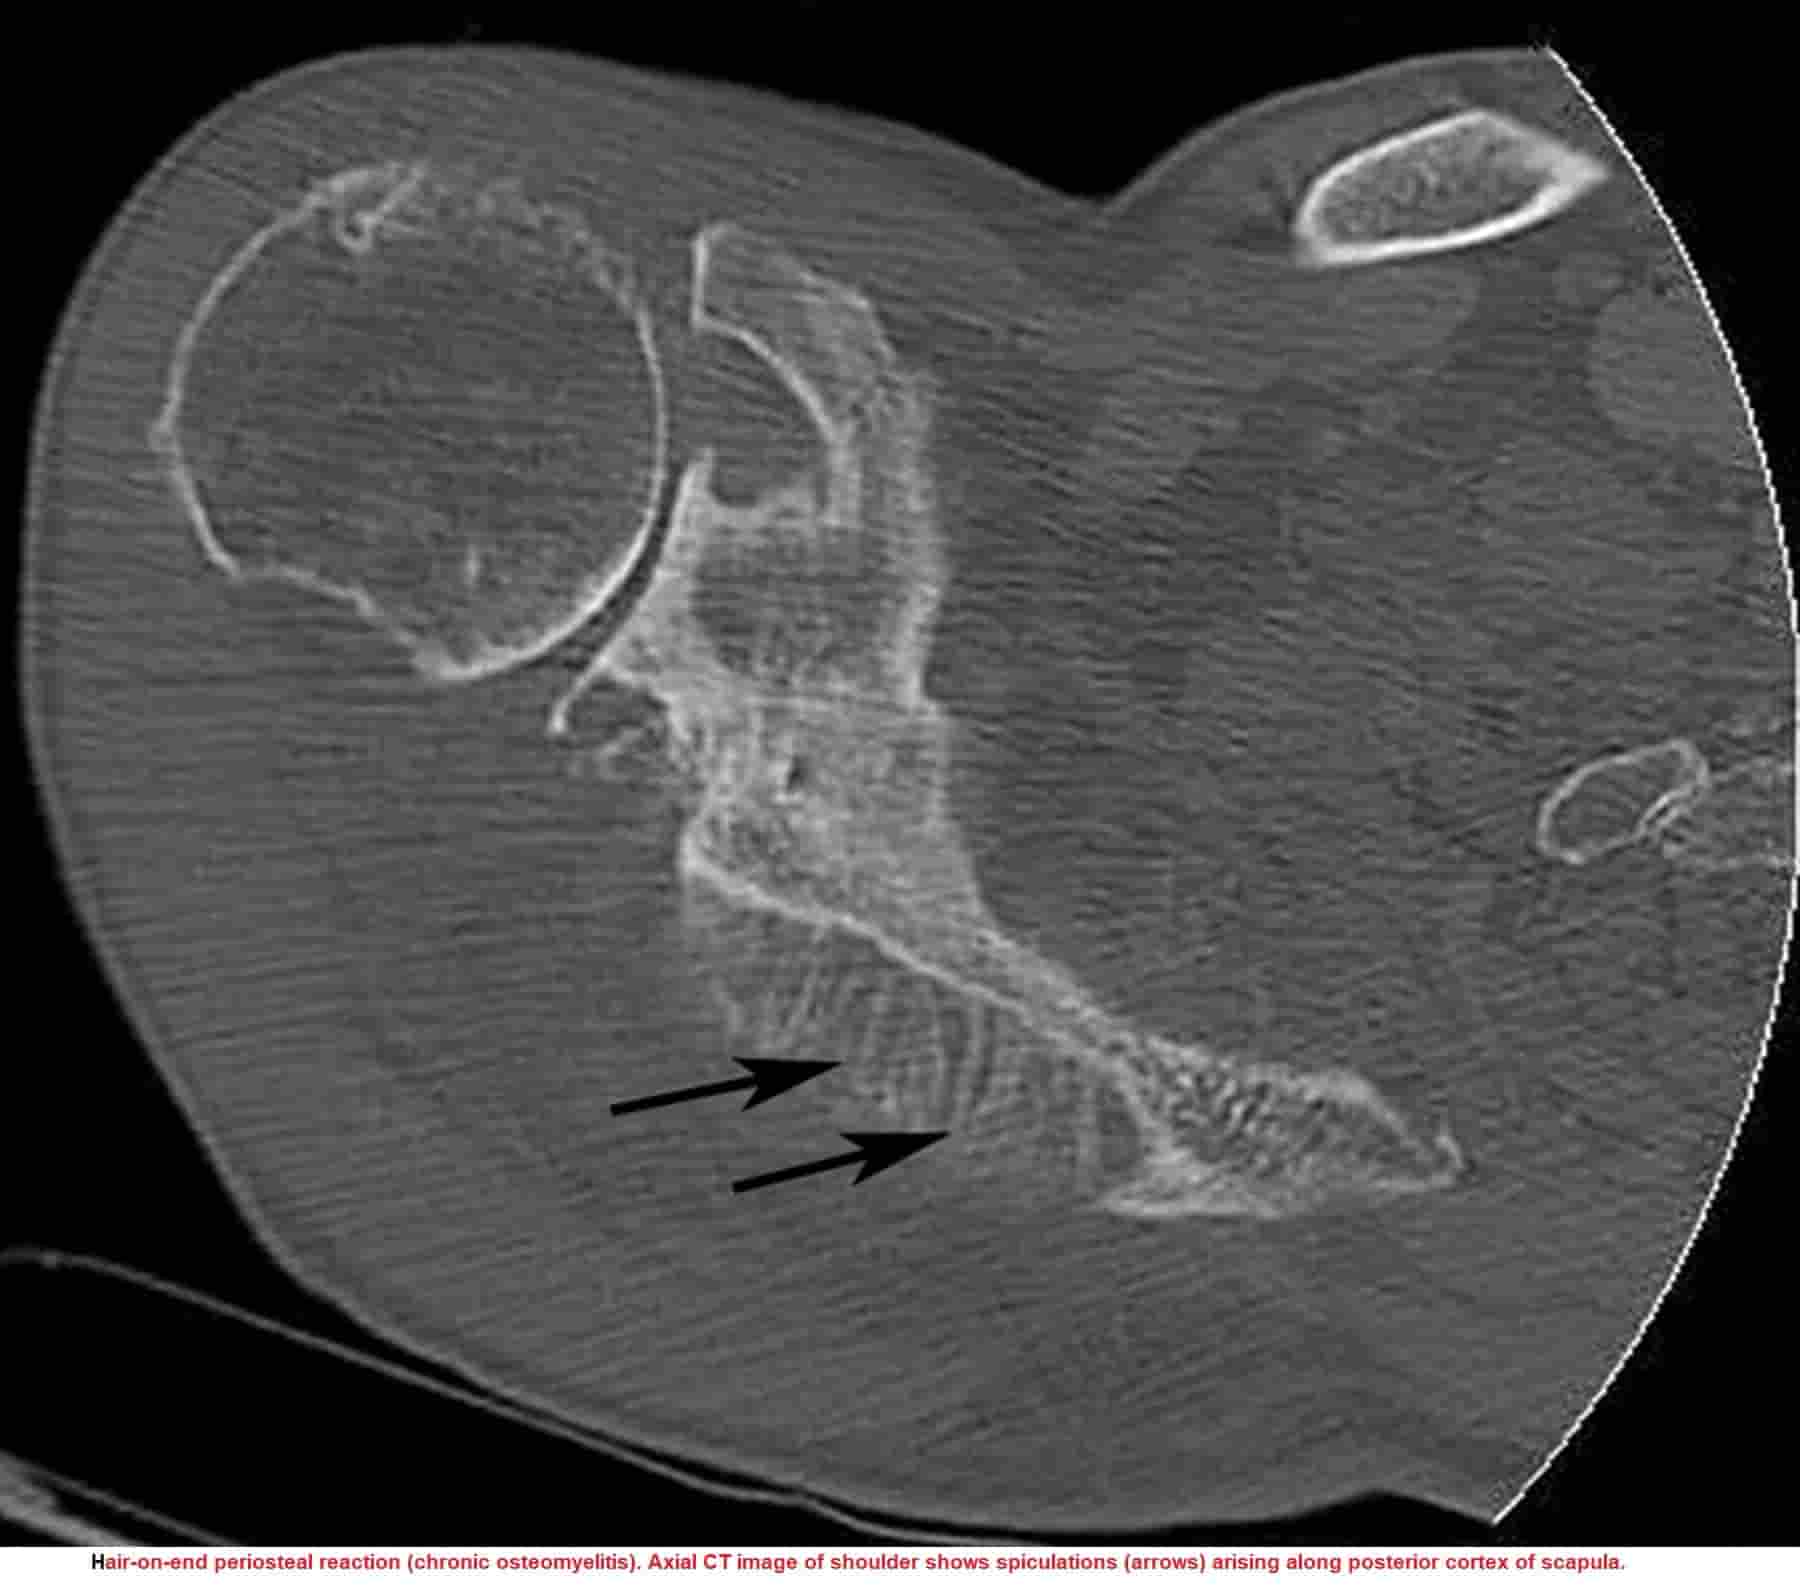

Periosteal Bone Formation Radiology. the inner cambium layer of periosteum responds to localized insult or injury by forming a new layer of bone along the surface of the underlying cortex; The periosteum is an important component of the bone growth, composing tissue unceasingly. the periosteal reaction occurs greatest near the center of the shaft and tapers toward the ends of the bone. Periosteal reaction can be divided into nonaggressive and aggressive morphologies. This new bone formation is called periosteal reaction. as the length of the bone is increasing due to the coordinated process of endochondral ossification and physeal. periosteal reaction refers to the elevation of periosteum from cortical bone and the subsequent deposition of new bone in this. Bone resorption and periosteal reaction. localized periosteal reaction develops that is indistinguishable from psoriatic arthritis but more commonly affects the lower extremities (such as the. besides covering the bone and sharing some of its blood supply with the bone, it also produces bone when it is stimulated appropriately.

as the length of the bone is increasing due to the coordinated process of endochondral ossification and physeal. periosteal reaction refers to the elevation of periosteum from cortical bone and the subsequent deposition of new bone in this. localized periosteal reaction develops that is indistinguishable from psoriatic arthritis but more commonly affects the lower extremities (such as the. The periosteum is an important component of the bone growth, composing tissue unceasingly. This new bone formation is called periosteal reaction. besides covering the bone and sharing some of its blood supply with the bone, it also produces bone when it is stimulated appropriately. Bone resorption and periosteal reaction. the periosteal reaction occurs greatest near the center of the shaft and tapers toward the ends of the bone. Periosteal reaction can be divided into nonaggressive and aggressive morphologies. the inner cambium layer of periosteum responds to localized insult or injury by forming a new layer of bone along the surface of the underlying cortex;